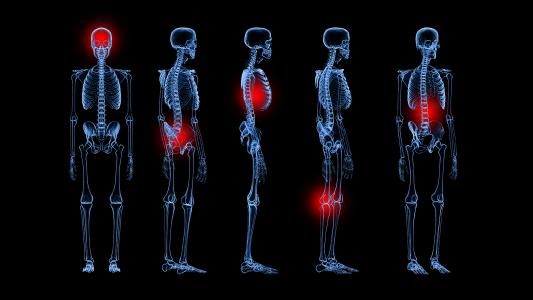

Robotic surgery is a game changer for minimally invasive surgery

In partnership with Intuitive

More and more surgeons are using robotic surgical systems. Here’s why.